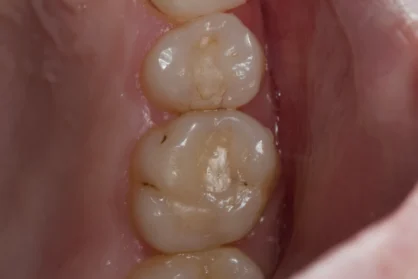

Приклади робіт лікаря-стоматолога

Естетична реставрація. До / після